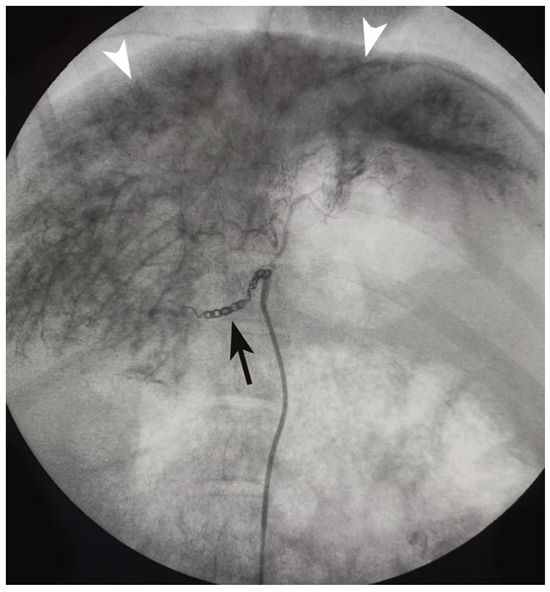

2.2. Liver Fibrosis Induction

- Gaba, R.C.; Mendoza-Elias, N.; Regan, D.P.; Garcia, K.D.; Lokken, R.P.; Schwind, R.M.; Eichner, M.; Thomas, F.M.; Rund, L.A.; Schook, L.B.; et al. Characterization of an Inducible Alcoholic Liver Fibrosis Model for Hepatocellular Carcinoma Investigation in a Transgenic Porcine Tumorigenic Platform. J. Vasc. Interv. Radiol. 2018, 29, 1194–1202.e1. [Google Scholar] [CrossRef]